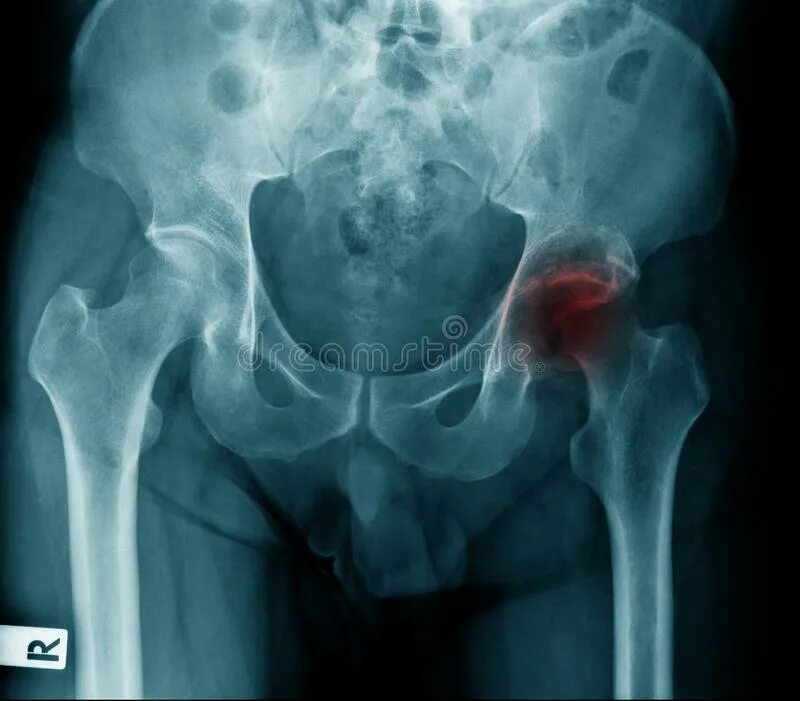

Некроз тазобедренного сустава лечение без операции